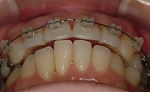

☆審美ワイヤー(光拡散型)の使用例と

ホワイトワイヤー(コーティング)での治療例

審美ホワイトワイヤー

光拡散ロジウムコートtypeワイヤー

ゴールドシリーズ審美ワイヤー

ホワイトコーティングtypeワイヤー